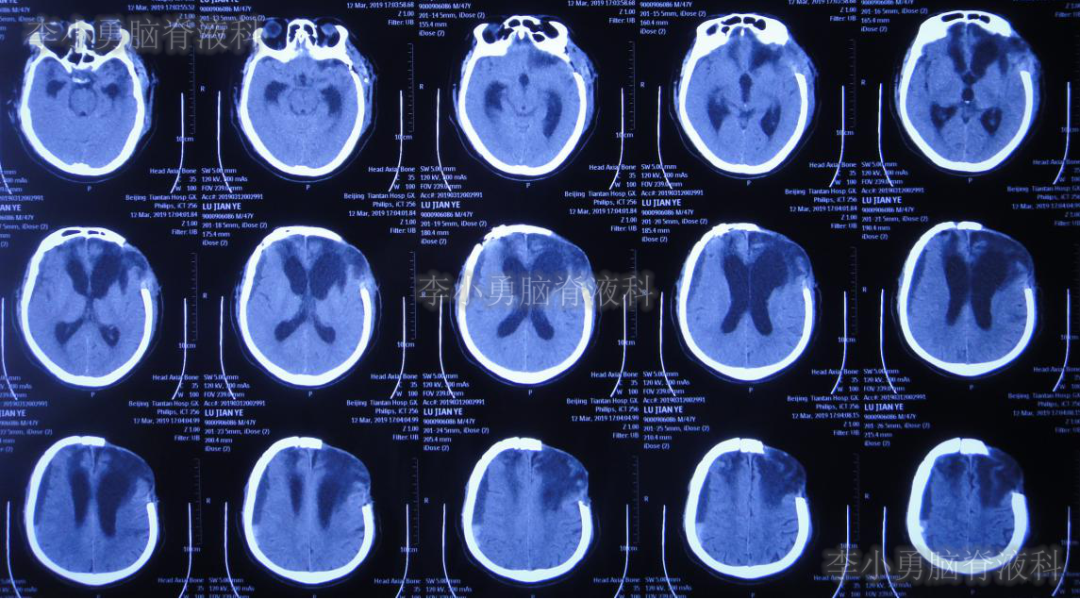

颅骨修补术+脑室腹腔分流术后105天即2019年7月12日(脑外伤术后194天),转至李小勇脑脊液科。入院时:患者呈昏迷状态,体温高,留置胃管、气管切开套管(图-9)。入院当天行头颅CT(图-10)示脑室扩张、腹部CT检查(图-11)可见肝区巨大的囊肿,其内可见引流管,考虑囊肿内为脑脊液。

图-10:2019年7月12日入院时头颅CT

由于患者脑室明显扩大,且肝区巨大水囊(引流管包裹形成),考虑分流管已发生堵塞,故入院当天紧急行脑室外引流术+原分流管拔除术。术后次日复查头颅CT(图-12)示引流管位置良好,无出血。

图-12:2019年7月13日头颅CT

术中留取的脑脊液标本培养5天后回报为表皮葡萄球菌,给予抗感染治疗。经过20天的治疗,患者脑脊液中细菌消失,且发热症状消失。于2019年8月6日常规复查头颅CT(图-15)示脑室略缩小,当日改行脑室长程引流术。

图-15:2019年8月6日头颅CT术前复查

术后常规复查头颅CT(图-16)示引流管位置良好。

图-16:2019年8月6日头颅CT术后复查